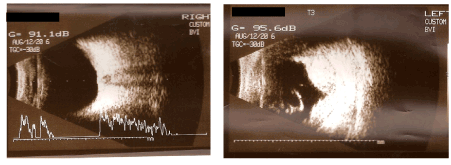

48-year-old man was admitted during emergency because of bilateral OGI; car window cut both eyeballs and skin of nose. On admission: Vod = hand motion(HM) Vos = questionable light perception(LP). Oedema, haematoma and small wounds of upper lids. Right eye (RE): Congestion of conjunctiva. Cornea with horizontal wound in the central part and vertical at the nasal part of limbus. Hyphema. No possibility to examine other eye structures. Left Eye (LE): Congestion of conjunctiva. Cornea with horizontal wound in the central part and prolapsed iris and vitreus. Intraocular haemorrhage. No possibility to examine other eye structures. Ultrasound examination (USG) revealed: RE: no pathologies with lens and posterior eye segment. LE: lack of lens, intraocular and subrerinal haemorrhages (Figure 1).

Figure 1b. Data on admission: USG examination.

Patient was discharged with Vod = 0.5/50 Vos = Fingers Counting (FC). RE: Congestion. Corneal wounds sutured, hyphema of the lower part of anterior chamber, oval pupil with synechiae, lens opacification. LE: Congestion. Corneal wound sutured. Intrabulbar blood clot mixed with vitreus. Posterior segments not available for examination. USG showed RE: no pathologies of posterior eye segment, LE: absorption of vitreal and subretinal haemorrhages (Figure 2).

Figure 2. USG examination on discharge day